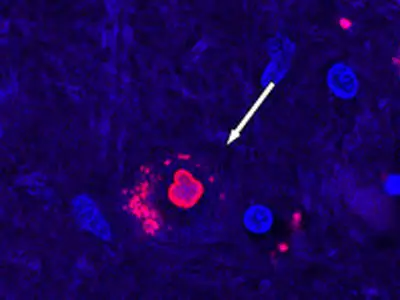

دانشمندان ایرانی و چکی با همکاری یکدیگر، حسگری مبتنی بر نانوتکنولوژی طراحی کردهاند که میتواند نشانگرهای زیستی بیماری پارکینسون را در بزاق شناسایی کند. این نوآوری، امیدی تازه برای تشخیص سریع و غیرتهاجمی این بیماری عصبی ایجاد کرده است.